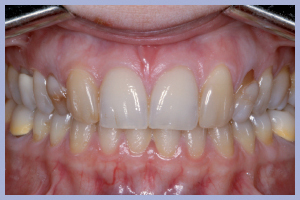

La valutazione clinica al momento della consegna dei manufatti e clinico-radiologica a 3 mesi dalla consegna manifestava una completa integrazione tissutale con eccellente recupero estetico e funzionale (Figg. 29-30).

- Figg. 28a, b – Confronto tra inizio e fine trattamento

- Figg. 29a, b Manufatti di destra e radiografia di controllo. Si noti l’ottima integrazione tissutale

- Figg. 30a, b – Manufatti di sinistra e radiografia di controllo